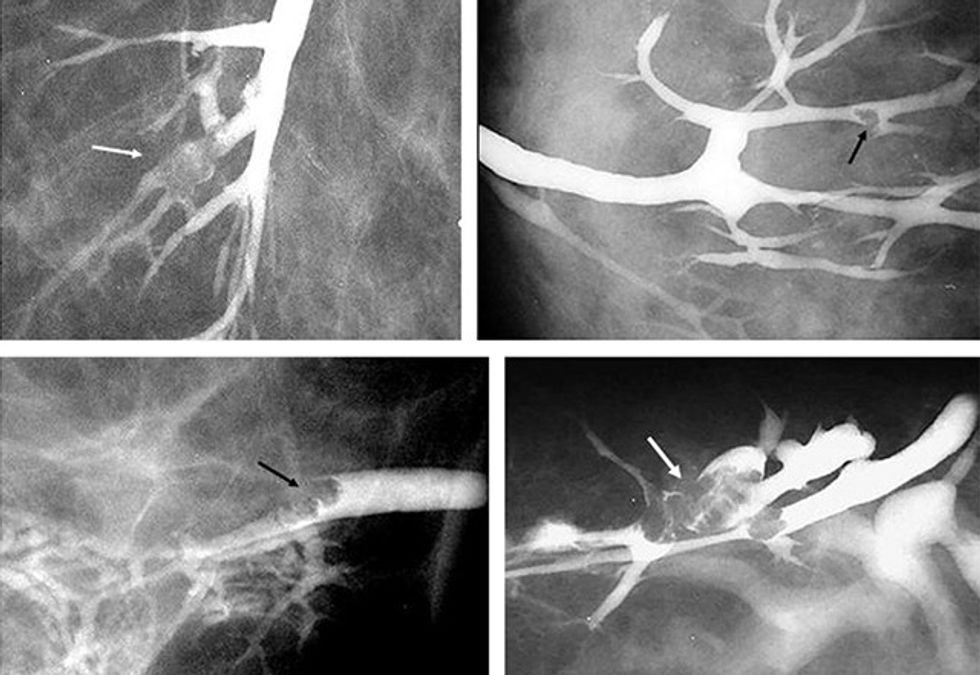

Galaktografia është metodë joinvazive me kontrast, qëllimi i së cilës është zbulimi i ndërrimeve intrakanalikulare në gjinj, të cilat me metoda tjera nuk mund të zbulohen). Sipas disa autorëve, prej 3% deri në 15% të rasteve, sekrecioni me ngjyrë të kuqe, të tejdukshme, mund të jetë një ndër shenjat e ekzistimit të tumorit malinj në duktus. Në mamografinë e fituar vërejmë fotografinë e kanaleve të mbushura me kontrast dhe në bazë të ndërrimeve eventuale, vihet diagnoza.